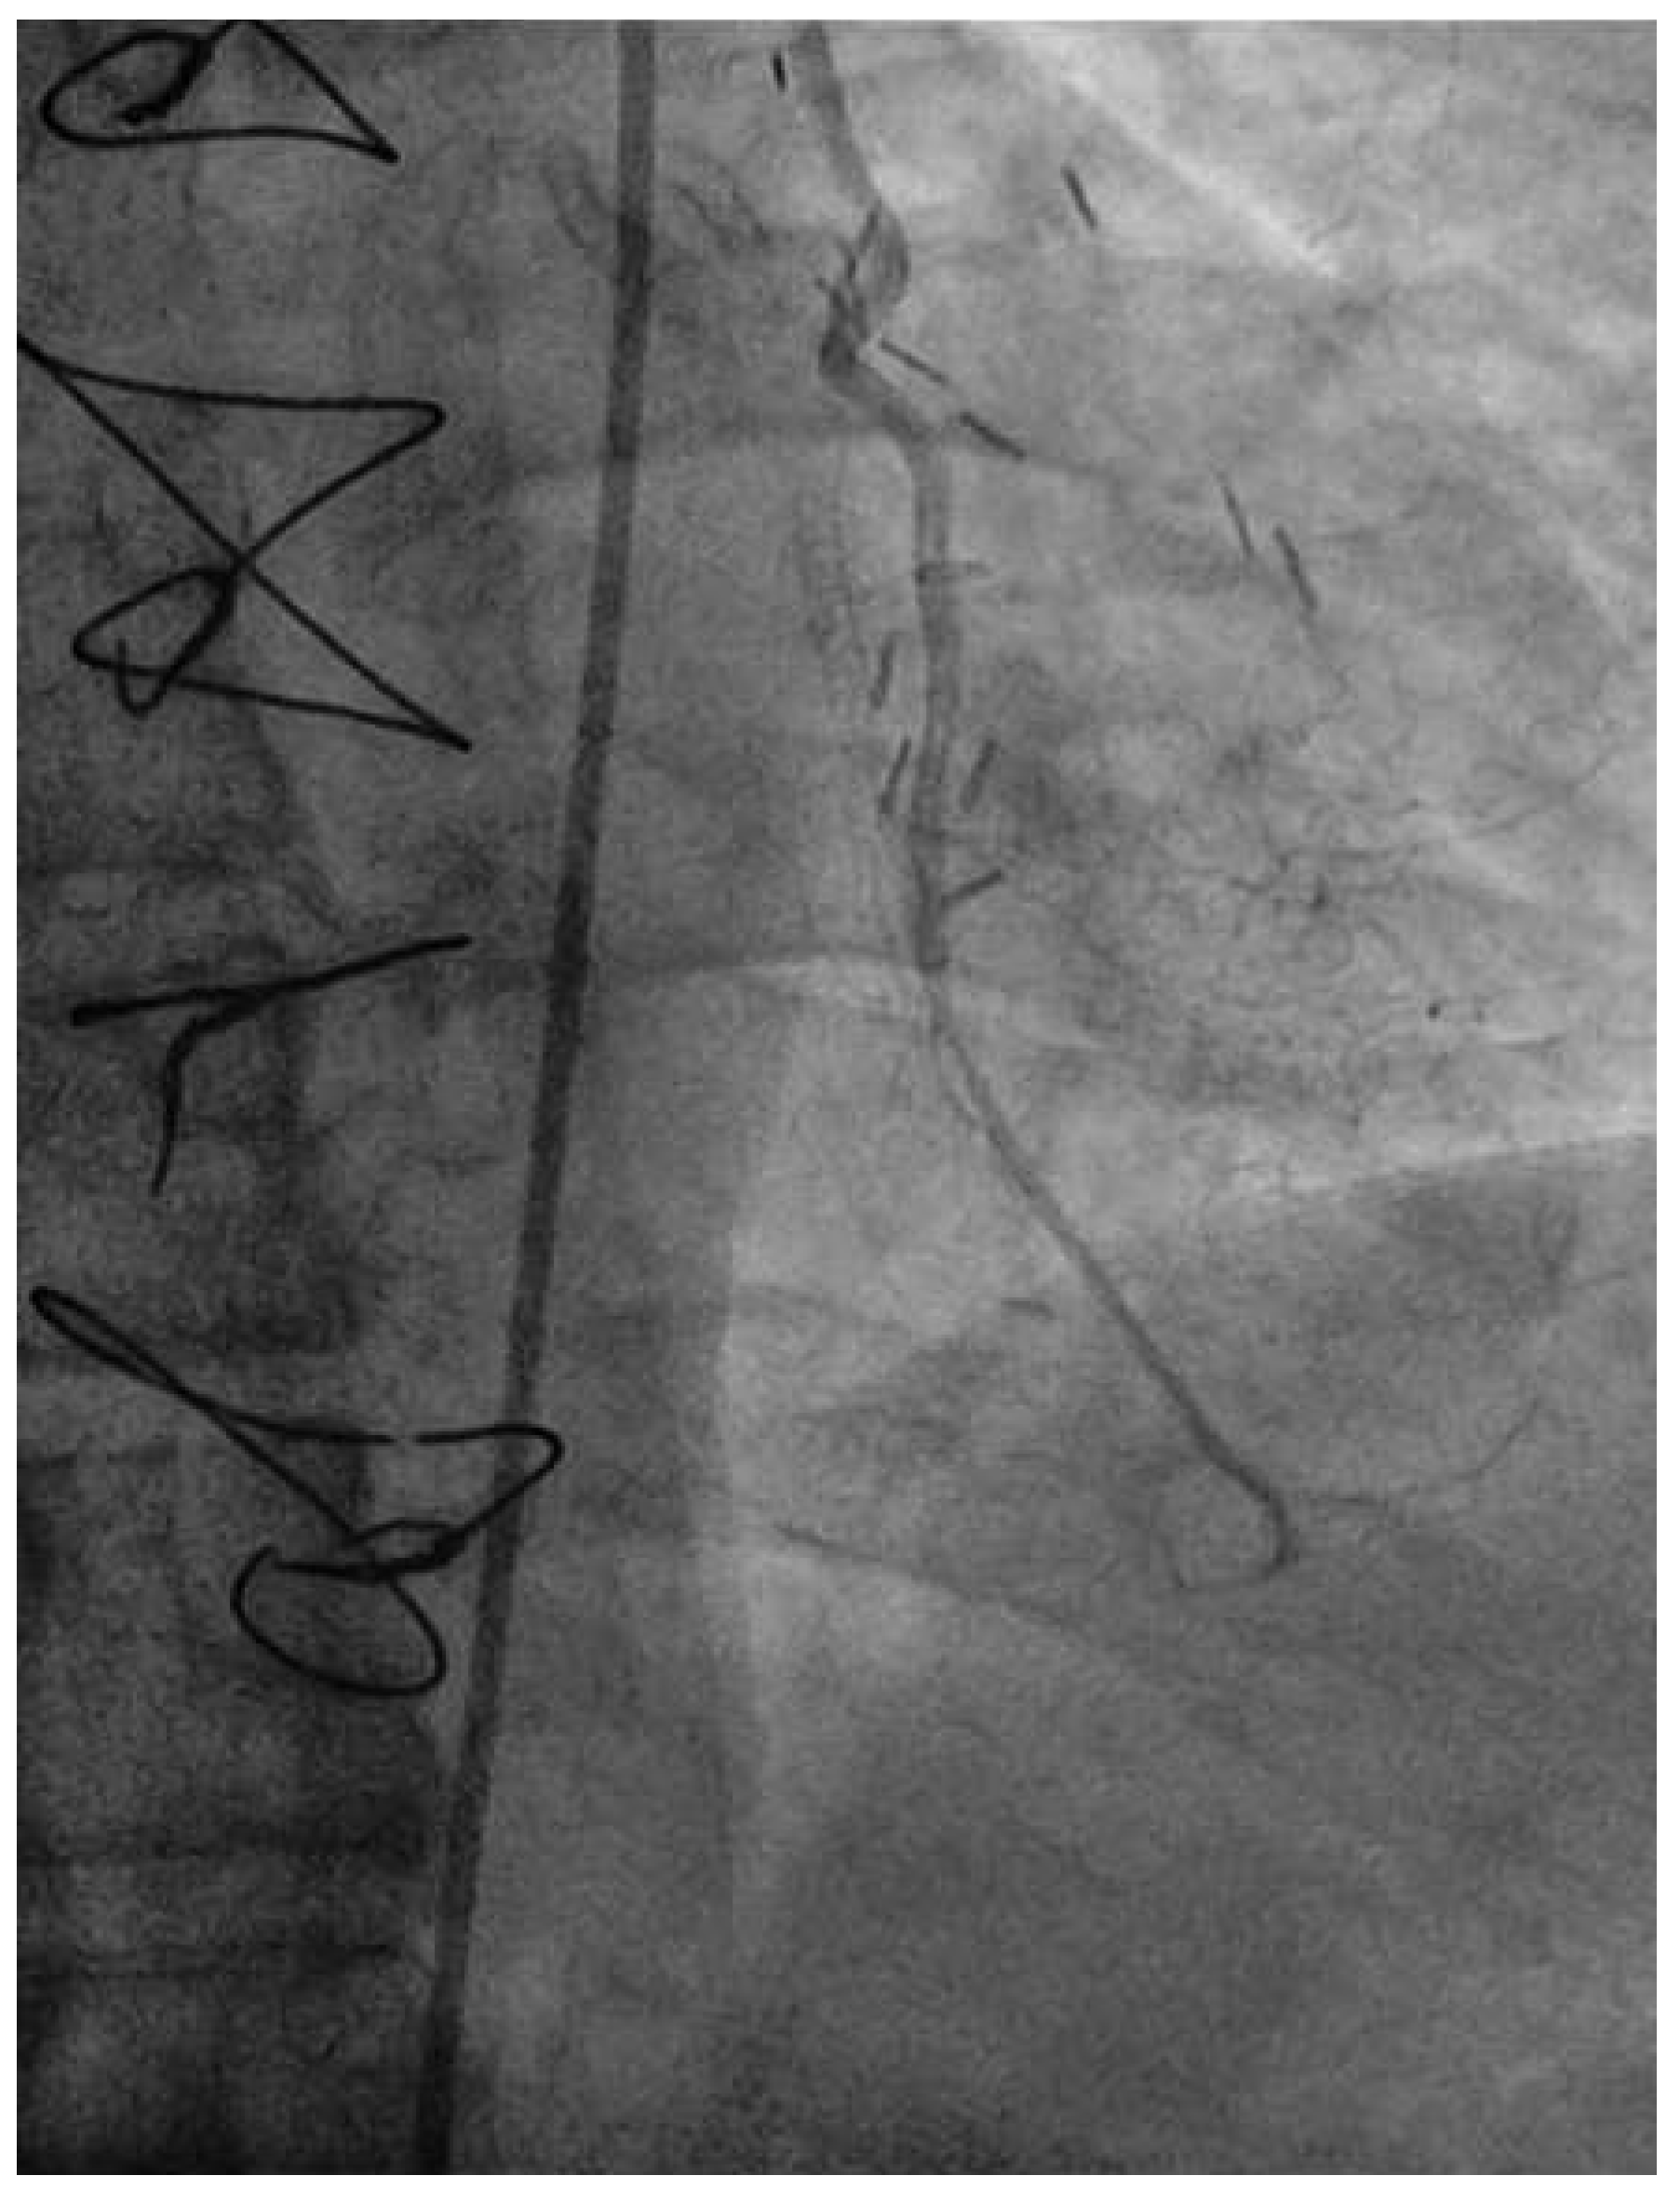

Following RA, both LAD and diagonal were wired with ease using separate Runthrough (Terumo, Japan) wires. Predilatation of both bifurcation limbs was undertaken using 1.5 × 15 mm Trek (Abbott) and 2.0 × 10 mm Sapphire (Orbus-Neich, Hong Kong, China) semicompliant balloons, which both expanded well at nominal pressure. Intending to perform an elective T-stent strategy, a 2.25 × 28 mm Promus Premier DES was deployed at 18 Atm in the diagonal branch, landing proximally at the ostium of this vessel (Figure 3). After removal of the diagonal wire, a 3 × 38 Promus Premier stent (Boston Scientific) was sited from the origin of the LMS across the first diagonal and deployed at 18 Atm (Figure 4). The diagonal branch was then rewired with the runthrough wire. A kissing inflation was performed at 12 Atm using a 3.5 × 12 Quantum (Boston Scientific) and 2.5 × 12 Sapphire noncompliant (NC) balloons in LAD and diagonal, respectively (Figure 5A). The proximal LAD and LMS were then optimised using the 3.5 Quantum NC (LAD) and a Hiryu (Terumo) 4 × 10 NC (LMS) balloons at 22 and 18 Atm, respectively (Figure 5B). The final angiographic result was excellent (Figure 6). Intravascular ultrasound of the LMS was not undertaken as angiographically the LMS stent already appeared completely expanded and oversized. We opted not to intervene in the ostial left Cx in order to best preserve the geometry of the LMS stent.

Haemostasis was achieved using manual digital compression 6 hours after heparin. The total fluoroscopy time was 16.4 min, total contrast 110 ml Iopamiro 370 (Bracco S.p.A., Feretinoa, Italy). Our patient was returned to the ward for overnight observation and discharged home the following day. He remains symptom-free at 3-month follow-up.

Figure 6. LAO 30°, cranial 30° views of final angiographic result.